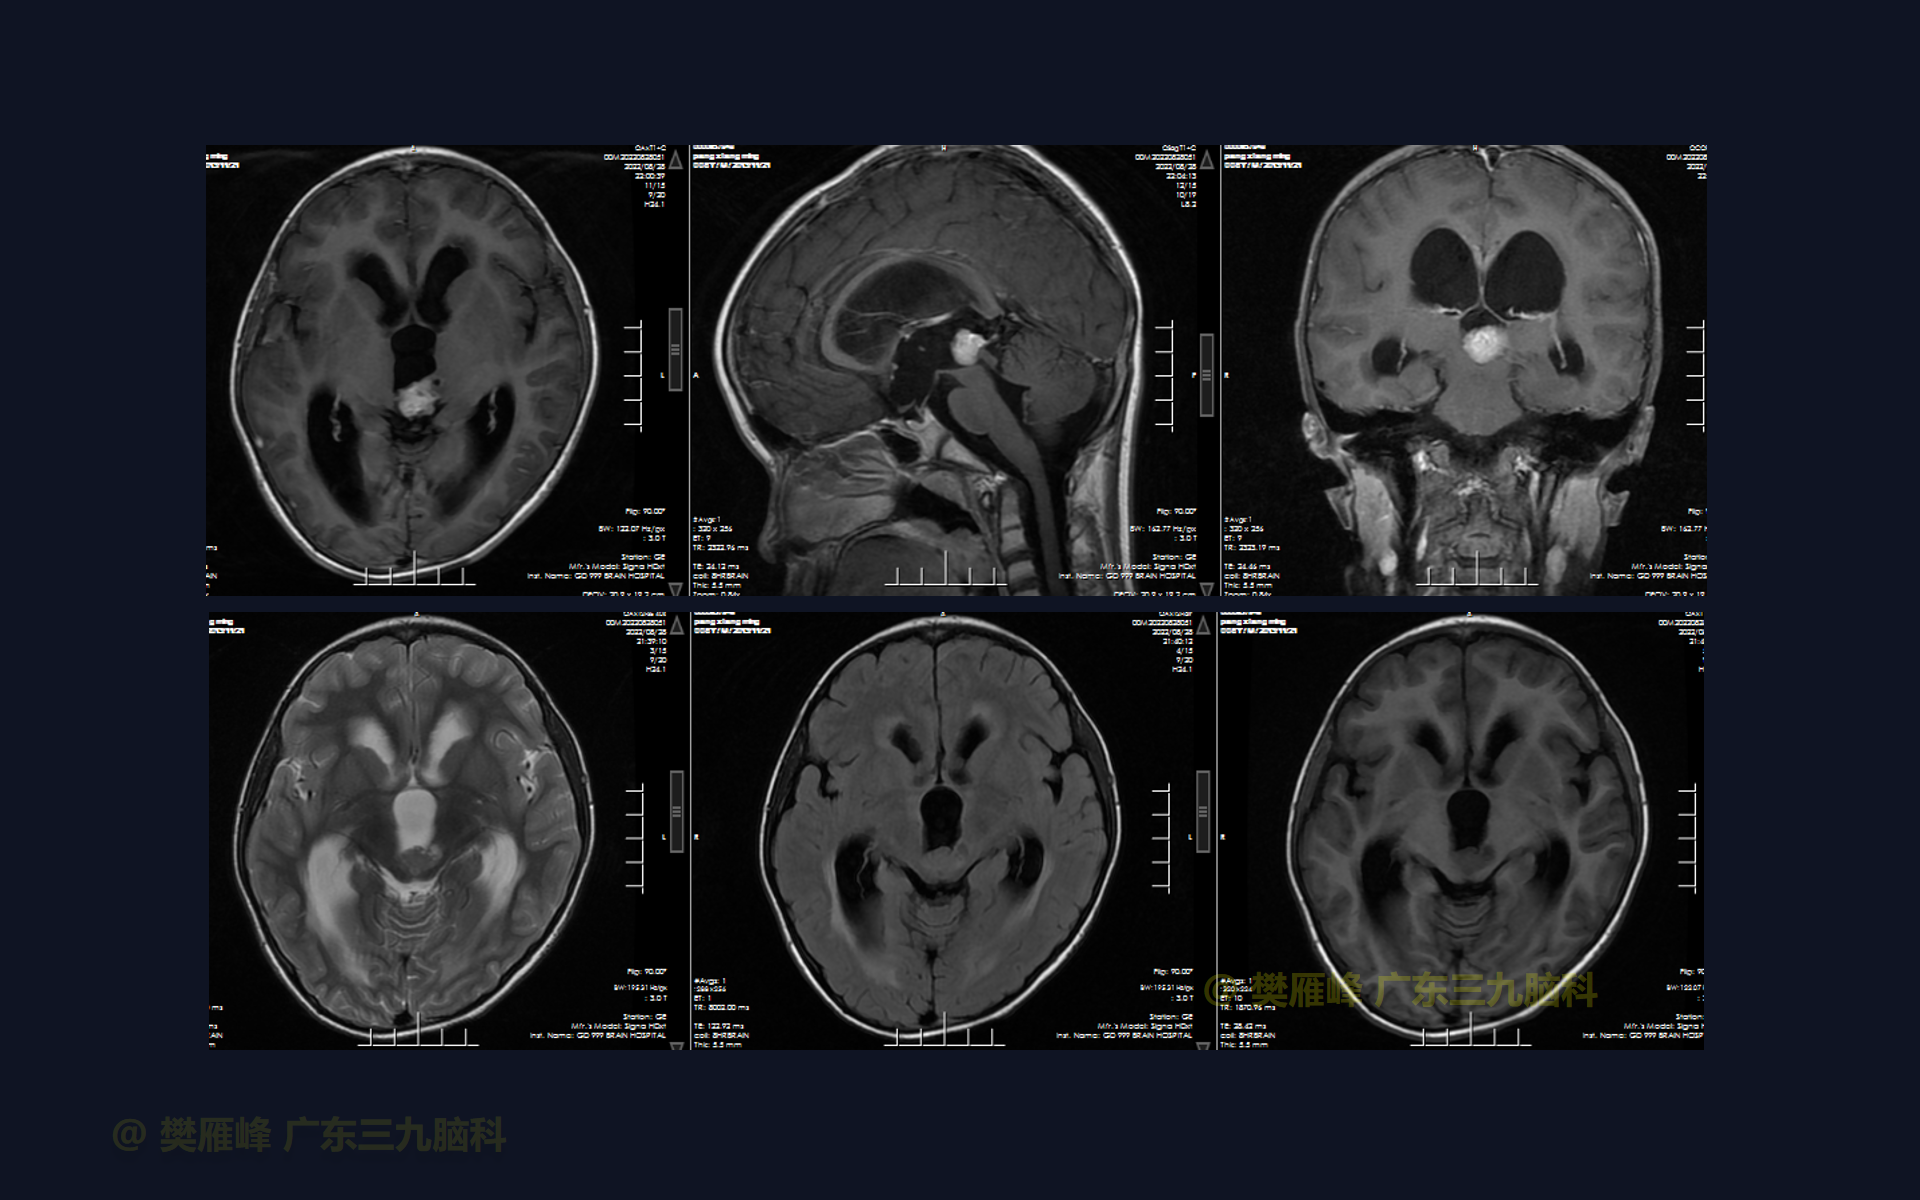

在这个二维手术视频中,展示了2例神经内镜下三脑室底造瘘+活检治疗三脑室后部肿瘤的方法。患者均为三脑室后部病变导致的梗阻性脑积水,病理结果1例为生殖细胞瘤,1例为淋巴瘤,在经过术后的放化疗病情均得到控制,生活质量满意。我们展示了安全的病变活检和第三脑室造瘘的技术要点,以最大限度减少术后继发脑积水和早期并发症。